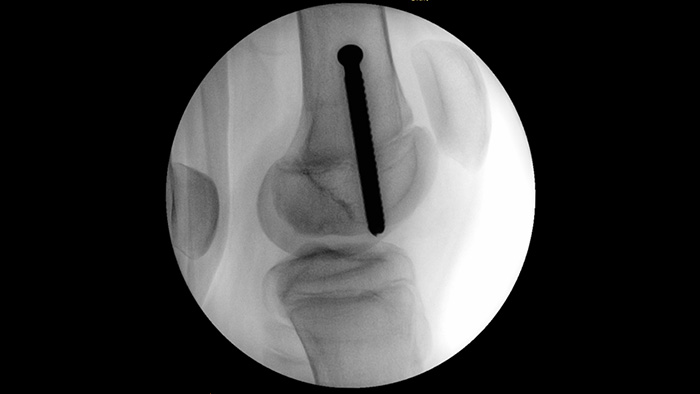

MetalSmart автоматически исключает металлические артефакты, вызванные наличием металлических имплантатов, чтобы обеспечить более высокое качество изображения и эффективный контроль дозы при проведении ортопедических процедур и обследовании пациентов с металлическими имплантатами. Это отличает данную систему от систем без опции исключения металлических артефактов. BodySmart способствует получению правильных изображений и значений эффективности дозы с первого раза, автоматически адаптируя область измерения к исследуемой области.